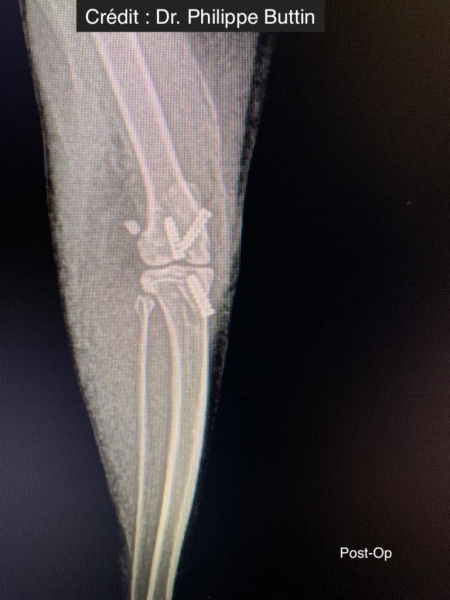

Mimokloubní stabilizace, která je dlouhodobě pevná, bez uzlů a zvlnění.

V případě ruptury kraniálního zkříženého vazu umožňuje ExtraTape® extraartikulární rekonstrukci co nejblíže izometrii původního vazu, čímž rychle a trvale stabilizuje koleno bez uzlů a zvlnění, což je slabina tradičnějších technik extraartikulární stabilizace. Ty jsou zde nahrazeny pevným ukotvením kosti pomocí interferenčního šroubu.

Radiologické snímky